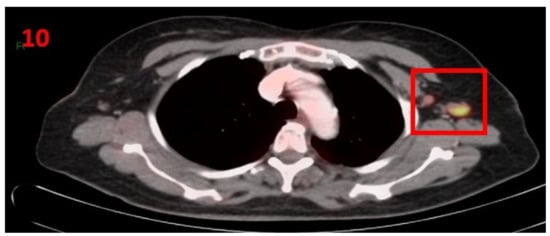

3.10. Case No 10

| Case no.10 | Breast cancer | Left arm | 5 days | Hypermetabolic uptake in the left axillary region and lymphadenopathy | Second vaccine | 11 mm | 4.5 | Pfizer-BioNTech |